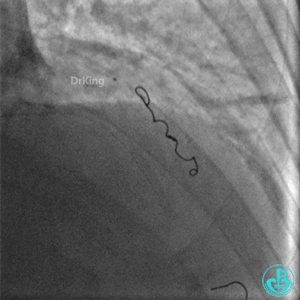

钝缘支分支远端破口完全闭塞。

明胶在血管怎么降解并发症丨前降支CTO同侧逆向开通时侧支血管破裂,弹簧圈联合明胶海绵封堵_https://www.jmylbn.com_新闻资讯_第53张

明胶在血管怎么降解并发症丨前降支CTO同侧逆向开通时侧支血管破裂,弹簧圈联合明胶海绵封堵_https://www.jmylbn.com_新闻资讯_第54张

封堵后观察半小时,患者血压逐步回升,维持在(100~110)/(50~60)mmHg,心率下降至90次/分。

明胶在血管怎么降解并发症丨前降支CTO同侧逆向开通时侧支血管破裂,弹簧圈联合明胶海绵封堵_https://www.jmylbn.com_新闻资讯_第55张

明胶在血管怎么降解并发症丨前降支CTO同侧逆向开通时侧支血管破裂,弹簧圈联合明胶海绵封堵_https://www.jmylbn.com_新闻资讯_第56张

出院随访

出院后1年复查造影,前降支支架通畅,血流3级。患者无明显胸闷、胸痛、喘憋等症状,日常活动不受限制。